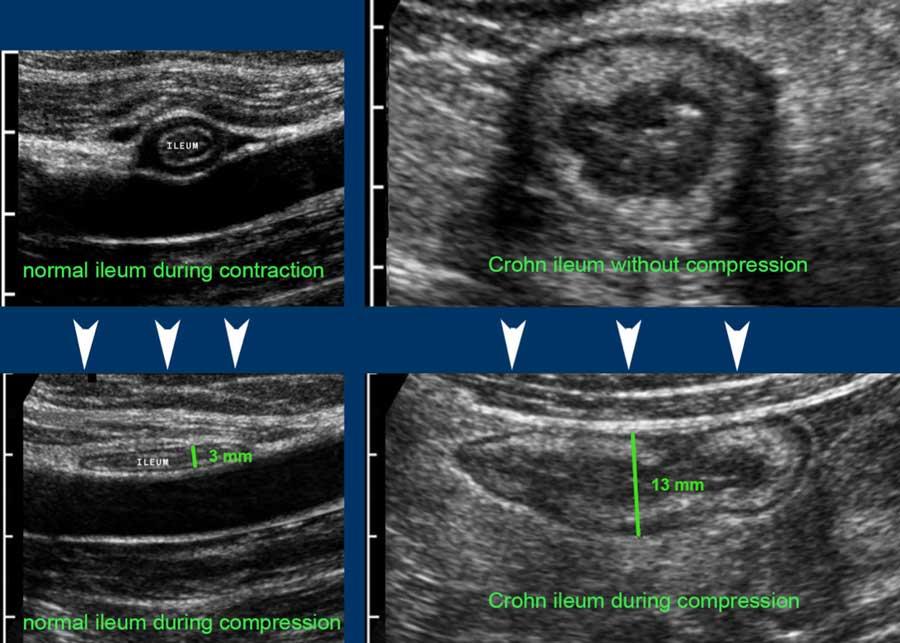

Ruột non bình thường có thể dễ dàng quan sát bằng siêu âm và được nhận biết qua nhu động ruột liên tục và rõ ràng, ngay cả khi lòng ruột trống rỗng.

Lưu ý nhiều vùng giảm âm nhỏ hình tròn với đường viền tăng âm trong lớp dưới niêm mạc sáng.

These represent normal 0.4 – 0.5 mm vessels.

Cũng lưu ý đường tăng âm mỏng bên trong lớp cơ, đại diện cho mô liên kết ngăn cách lớp cơ dọc và lớp cơ vòng, chứa đám rối Auerbach.

Normal small bowel in the longitudinal plane.